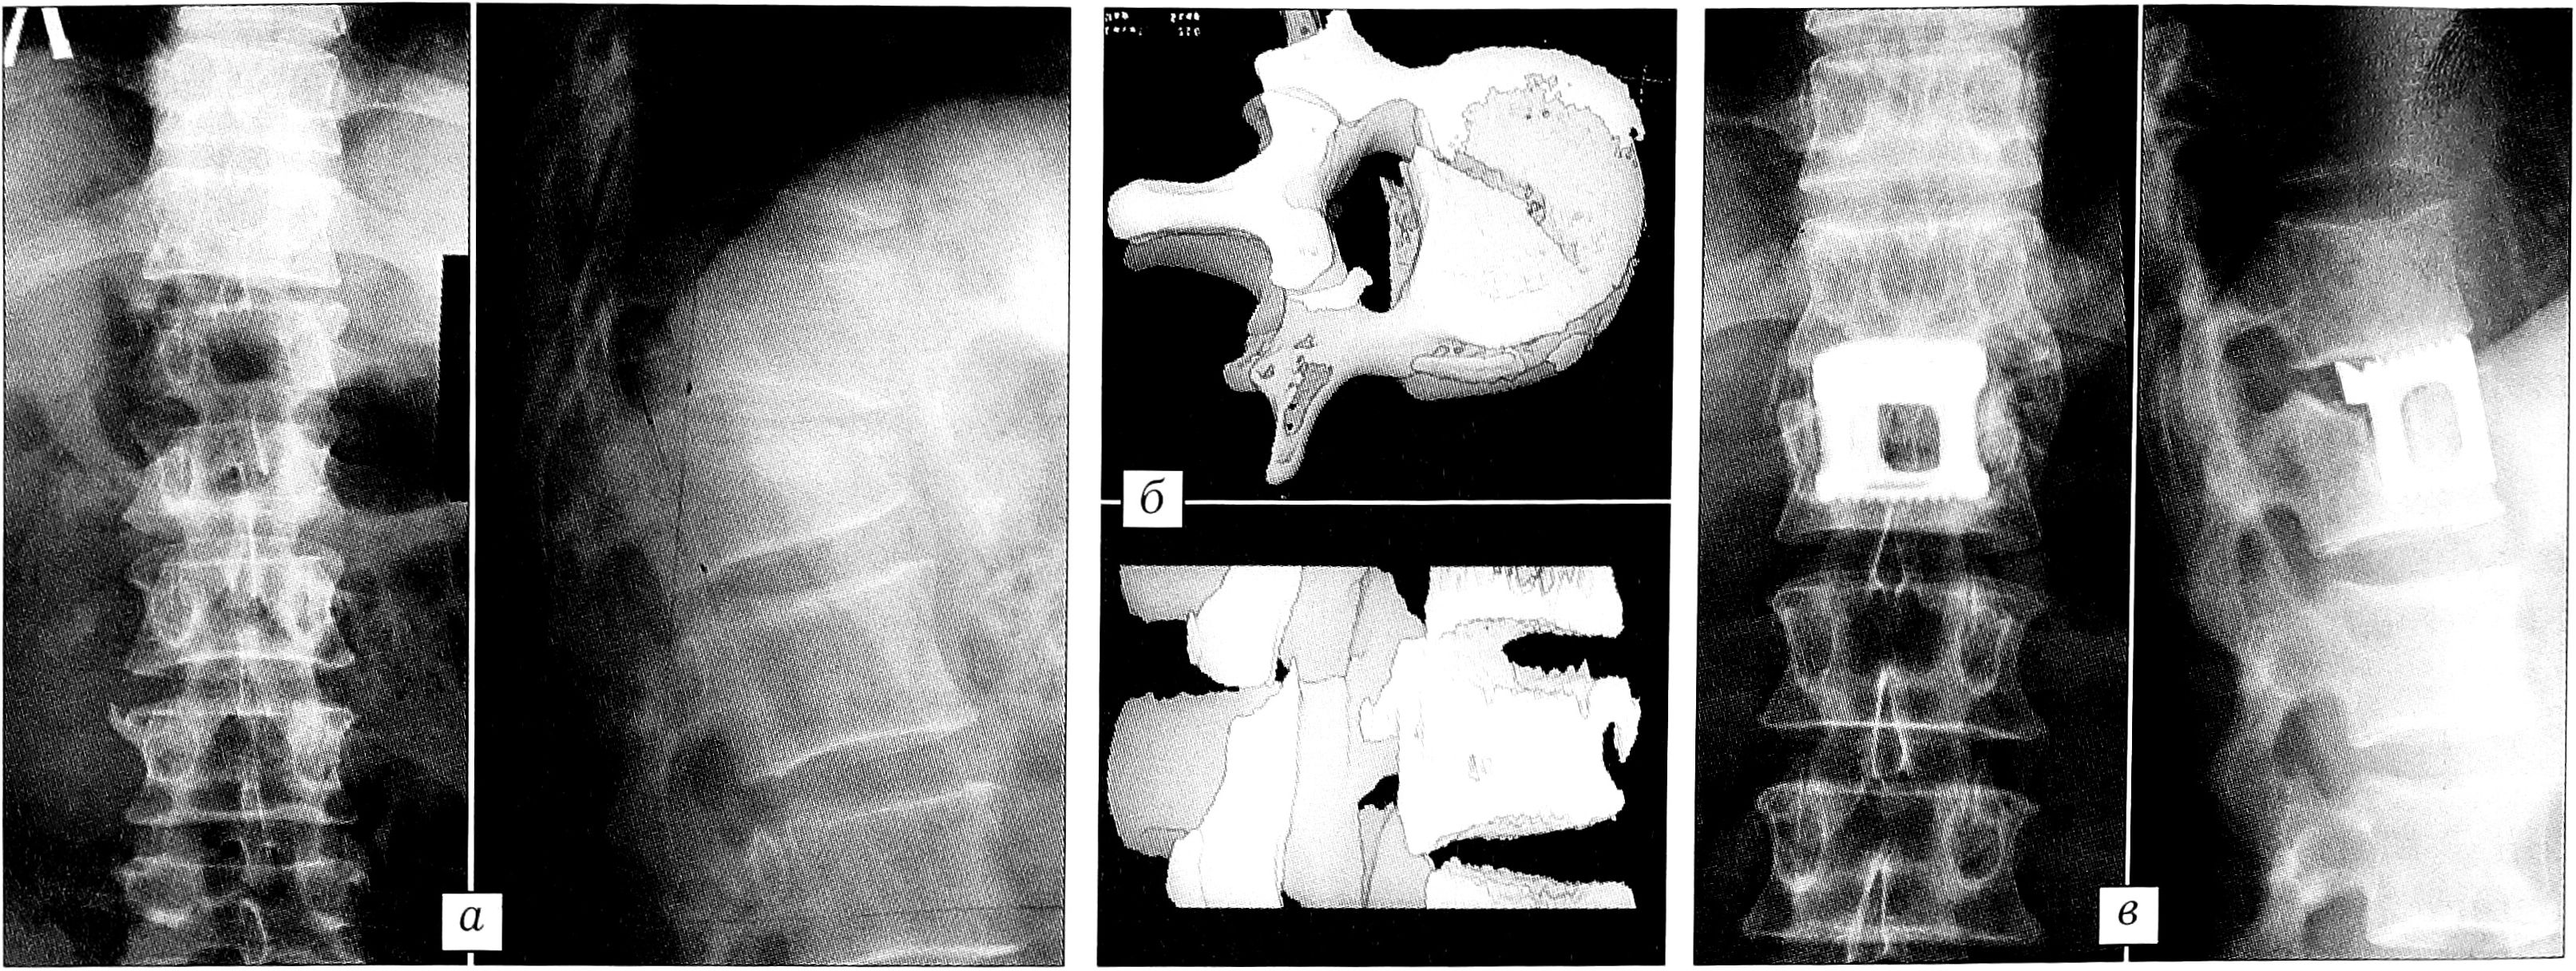

При оскольчатых вертикальных переломах тела позвонка без значительного разрушения и дислокации краниальной и каудальной замыкательных пластинок, флексионно-дистракционных горизонтальных переломах, проникающих переломах на фоне выраженного остеопороза достаточен корригирующий транспедикулярный остеосинтез, в случае выраженного остеопороза — дополненный спонгиозопластикой. При нестабильных взрывных переломах с выраженной дислокацией дорсального фрагмента в позвоночный канал, когда разрушены вентральная и средняя колонны — тип В (рис. 3), при ротационно-экстензионных переломовывихах позвонков — тип С (рис. 4) требуются выполняемые одномоментно или последовательно дорсальный корригирующий остеосинтез и вентральный спондилодез, при необходимости в сочетании с передней декомпрессией.

Рис. 3. Больной С. 49 лет. а — рентгенограммы до операции: неполный взрывной нестабильный перелом тела L1 позвонка; б — компьютерная томограмма до операции: дислокация дорсального фрагмента в позвоночный канал; в — рентгенограммы через 1 год после транспедикулярного остеосинтеза Т12-L2 позвонков, коррекции деформации позвоночного канала, аутопластики и моносегментарной эндофиксации.